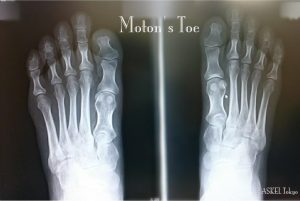

「痛みは足から始まる」の著者であるアメリカの外科医の90%の患者の踵の痛み、踵骨棘、足底腱膜炎の痛みの理由は、第一中足骨が短い足の骨格の方であることが解ったと著書の中に書かれている 先日、踵周辺と土踏まずの辺りが痛くて診 […]